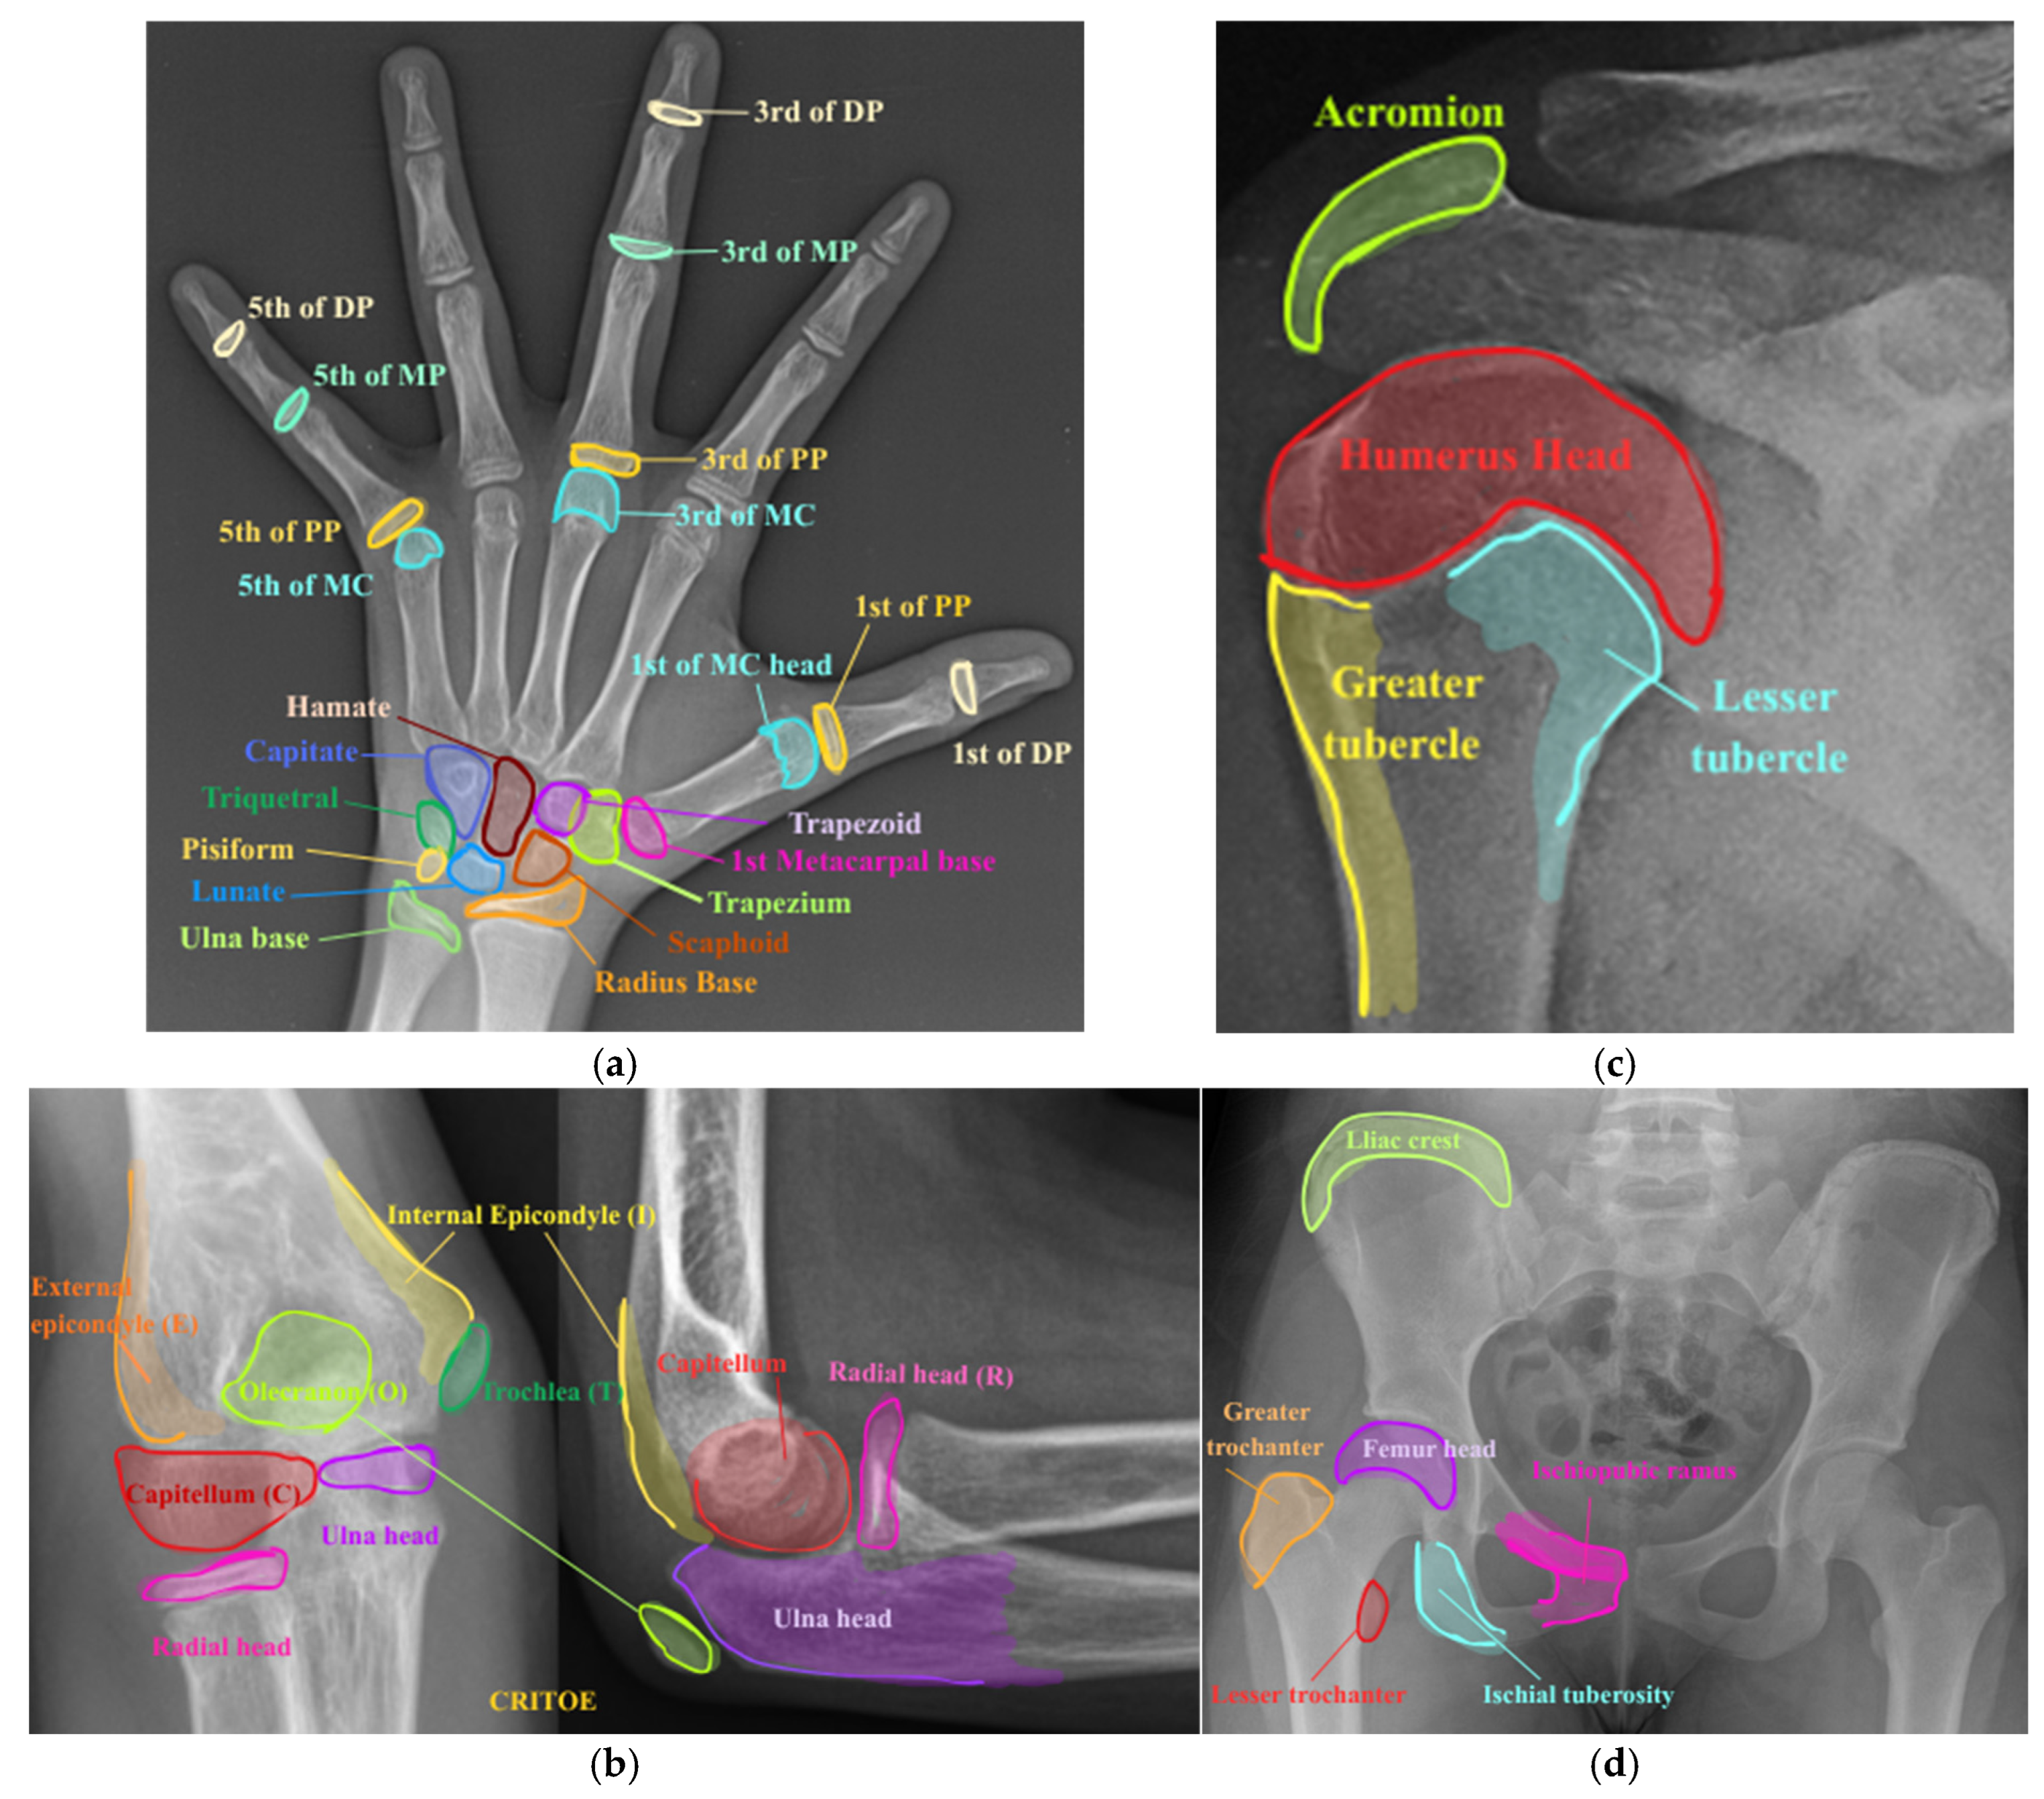

3.1. Preprocessing

3.2. Region-Based Symbolic Segmentation

4.1. Dataset

| CRITOE | capitellum, radius, internal epicondyle, trochlea, olecranon, external epicondyle |